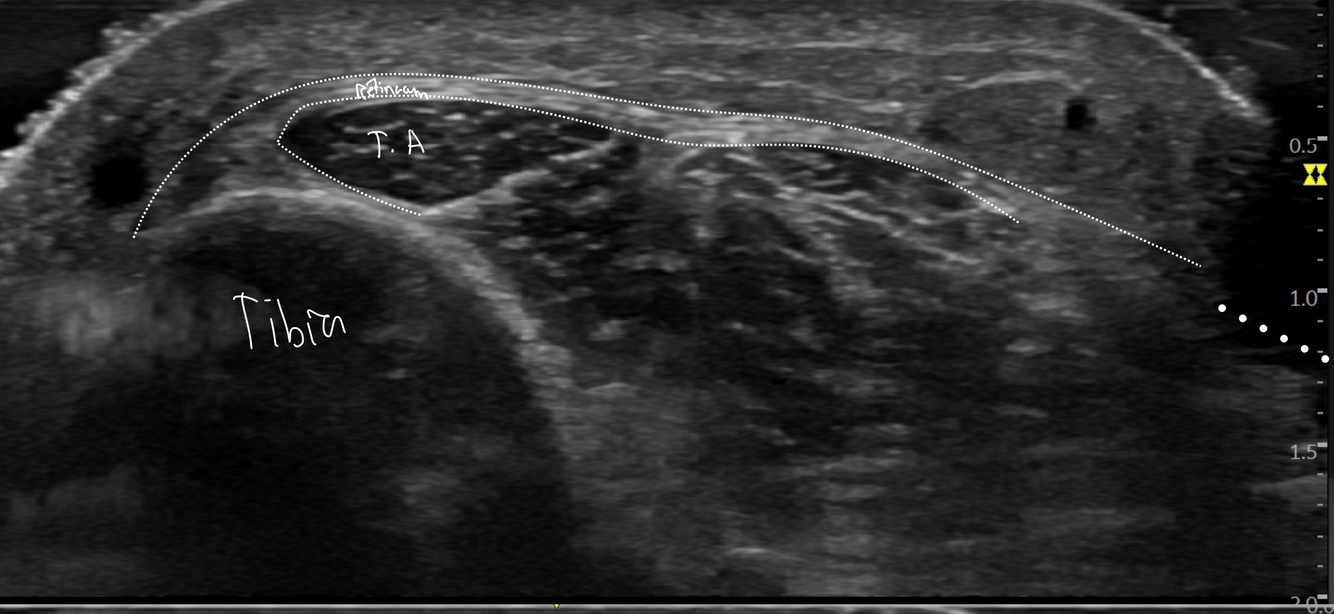

Identifier les structures suivantes

- Tibial post

- LFO

- Nerf tibial